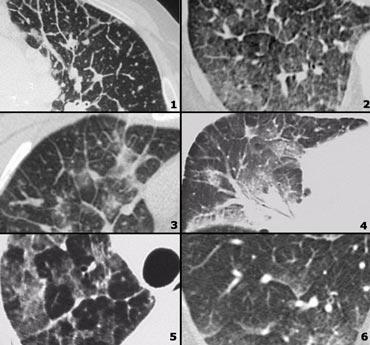

Examples of reticular pattern:

- Ung thư hạch bạch huyết: dày vách liên tiểu thùy không đều, thường khu trú hoặc một bên 50% có hạch to, có tiền sử ung thư.

- Phù phổi do tim: phát hiện tình cờ trên HRCT, dày vách liên tiểu thùy trơn láng với ưu thế ở vùng đáy (đường Kerley B), mờ kính mờ phân bố theo trọng lực và quanh rốn phổi, dày mô kẽ quanh bó mạch phế quản (dày bao quanh phế quản)

- Lymphangitic carcinomatosis

- Lymphangitic carcinomatosis with hilar adenopathy.

- Protein phế nang: tăng đậm độ dạng kính mờ kèm dày vách liên tiểu thùy (hình ảnh “crazy paving”).

- Cardiogenic pulmonary edema.

Examples of nodular pattern

- Viêm phổi quá mẫn: các nốt centrilobular không rõ ranh giới.

- Miliary TB: random nodules

- Sarcoidosis: các nốt phân bố quanh bạch mạch, dọc theo các khe liên thùy, hạch to.

- Viêm phổi quá mẫn: các nốt trung tâm tiểu thùy, lưu ý vùng kế cận màng phổi và khe liên thùy được bảo tồn.

More nodular pattern

- TB: Tree-in-bud appearance in a patient with active TB.

- Mô bào tế bào Langerhans: giai đoạn nốt sớm trước khi các nang điển hình xuất hiện.

- Respiratory bronchiolitis in infection.

Examples of High Attenuation pattern

- Viêm phổi tăng bạch cầu ái toan mạn tính với các vùng ngoại vi có đậm độ kính mờ.

- Sarcoid giai đoạn cuối với xơ hóa lan rộng ở thùy trên biểu hiện dưới dạng các vùng đông đặc. Lưu ý hạch to.

- Viêm phổi tăng bạch cầu ái toan mạn tính với các vùng đông đặc ngoại vi.

- Ung thư biểu mô phế nang phế quản với cả vùng kính mờ và đông đặc

High Attenuation pattern (2)

- Viêm phổi mô kẽ không đặc hiệu (NSIP): kính mờ kèm giãn phế quản do co kéo, không có tổn thương tổ ong.

- Cryptogenic organizing pneumonia (COP).

- Sarcoidosis giai đoạn cuối: đông đặc do xơ hóa lan rộng vùng quanh rốn phổi và thùy trên.

- COP.